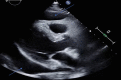

Abstract: Pembrolizumab is an immune checkpoint inhibitor used in various types of cancers. Pericardial tamponade is a rare side effect reported in only very few case reports. Early recognition and therapeutic intervention is vital in all cases. We report a case of a 54-year-old male with Stage 3 lung adenocarcinoma who developed cardiac tamponade secondary to pembrolizumab and subsequently required pericardial window.